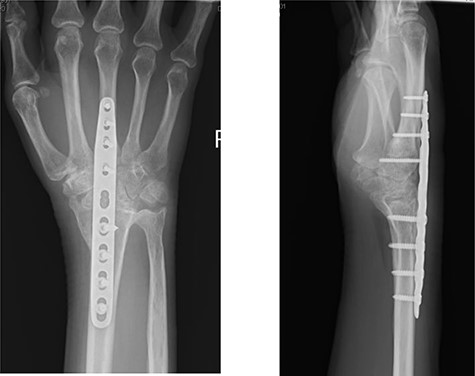

Radiographs demonstrated that the Pyrocarbon implant was palmarly displaced and rotated 90 degrees; it had migrated into the carpal tunnel/ distal forearm (Fig. 2). The clinical diagnosis was compression of the ulnar due to the migration of implant. Surgery was carried out 1 month later during which the Pyrocarbon Amandys wrist implant was removed through a volar approach (Fig. 3) and total wrist fusion was performed using a straight Arbeitsgemeinschaft für Osteosynthesefragen (AO) wrist fusion plate (Fig. 4). The surgery successfully relieved all wrist pain and was accompanied by prompt resolution of symptoms of ulnar nerve compression; she was discharged from follow-up approximately 3 months after surgery.

Post-operative radiographs following removal of pyrocarbon implant and total wrist fusion.